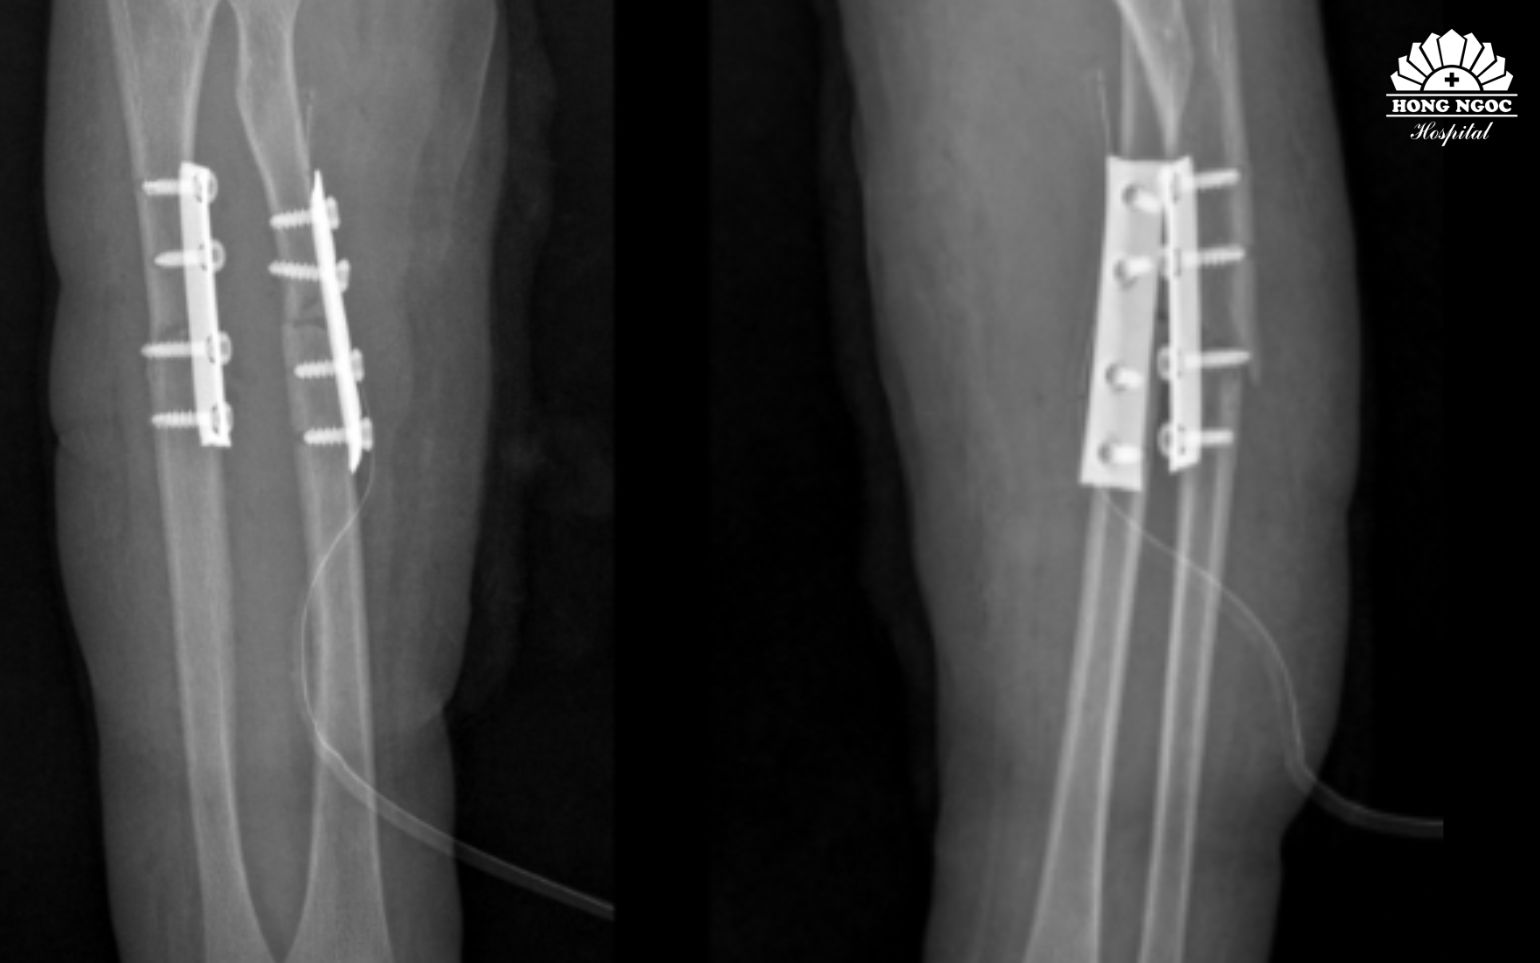

_1.jpg)

Phẫu thuật kết hợp xương cố định xương gãy, phục hồi vận động sớm

Sau hơn 1 giờ phẫu thuật, dưới sự hỗ trợ của hệ thống máy C-arm, ê-kíp phẫu thuật tiến hành nắn chỉnh trục xương giúp đưa hai đầu xương gãy và mảnh xương di lệch về đúng vị trí giải phẫu, khôi phục chiều dài và chức năng sấp, ngửa của cẳng tay. Sau đó, phẫu thuật viên đặt nẹp vít cố định nhằm giữ vững hai đoạn xương, tạo điều kiện cho quá trình liền xương diễn ra đúng vị trí giải phẫu, tránh nguy cơ sai lệch hoặc biến dạng. Toàn bộ quá trình phẫu thuật được thực hiện qua một đường mổ nhỏ ở phía trước. Chỉ với một đường tiếp cận này, phẫu thuật viên có thể nắn chỉnh và cố định đồng thời cả hai xương gãy, giúp giảm tổn thương phần mềm, hạn chế mất máu và giảm đau sau mổ cho bệnh nhi.